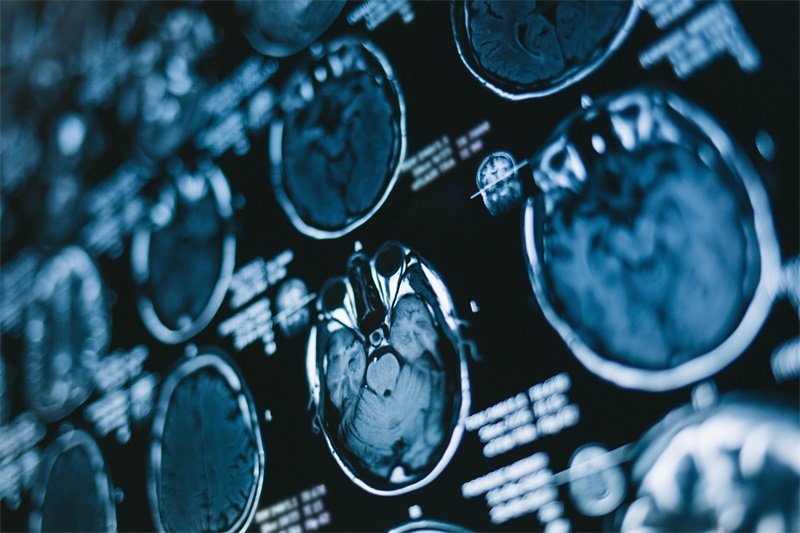

侧脑室的后角是大脑内部的一个特定区域,而“占位”则是指在这一区域内出现了异常的结构或肿块。这些占位可以是良性的,也可以是恶性的,了解其本质非常重要。通常,医生会通过影像学检查(如核磁共振或CT扫描)来判断是否存在占位,并进一步分析其性质。

影像学检查是诊断的首要步骤,核磁共振(MRI)和计算机断层扫描(CT)是最常用的方法。这些检查能够清晰地显示侧脑室及其周围结构的状态,从而确定是否存在占位及其大小、形态。

在影像检查中,医生会特别关注占位的边界、密度以及是否有其他伴随症状,结合临床表现来做出初步判断。